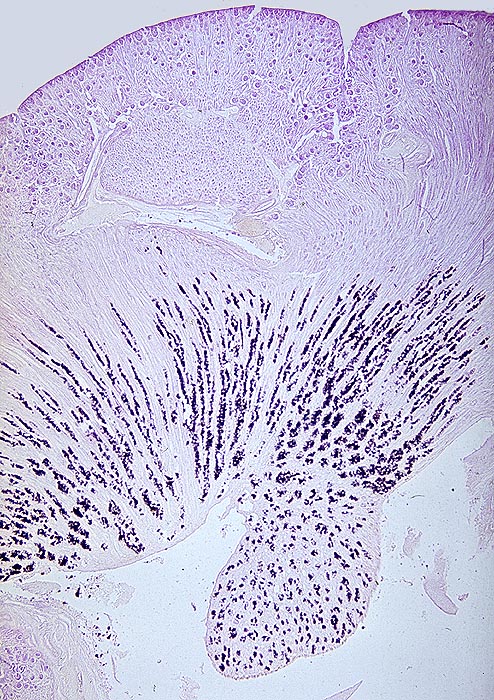

Akute Harnsäurenephropathie: Harnsäureinfarkte

Harnsäureinfarkte: massive Ausfällung von Harnsäure im Nierenmark bis zur Papillenspitze. Alkoholfixation und Harnsäure-Färbung.

Sekundäre akute Harnsäure Nephropathie bei erhöhtem Nukleinsäureumsatz, Enzymdefekten oder verminderter Harnsäureausscheidung.